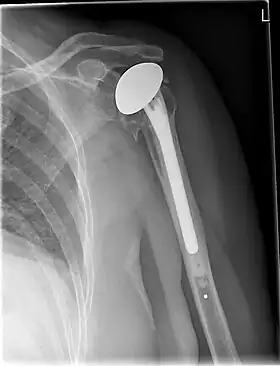

![]() X-ray of a shoulder prosthesis | |

Various materials can be used to make prostheses, however the majority consist of a metal ball that rotates within a polyethylene (plastic) socket. The metal ball takes the place of the patient's humeral head and is anchored via a stem, which is inserted down the shaft of the humerus. The plastic socket is placed over the patient's glenoid and is typically secured to the surrounding bone via cement.[11]